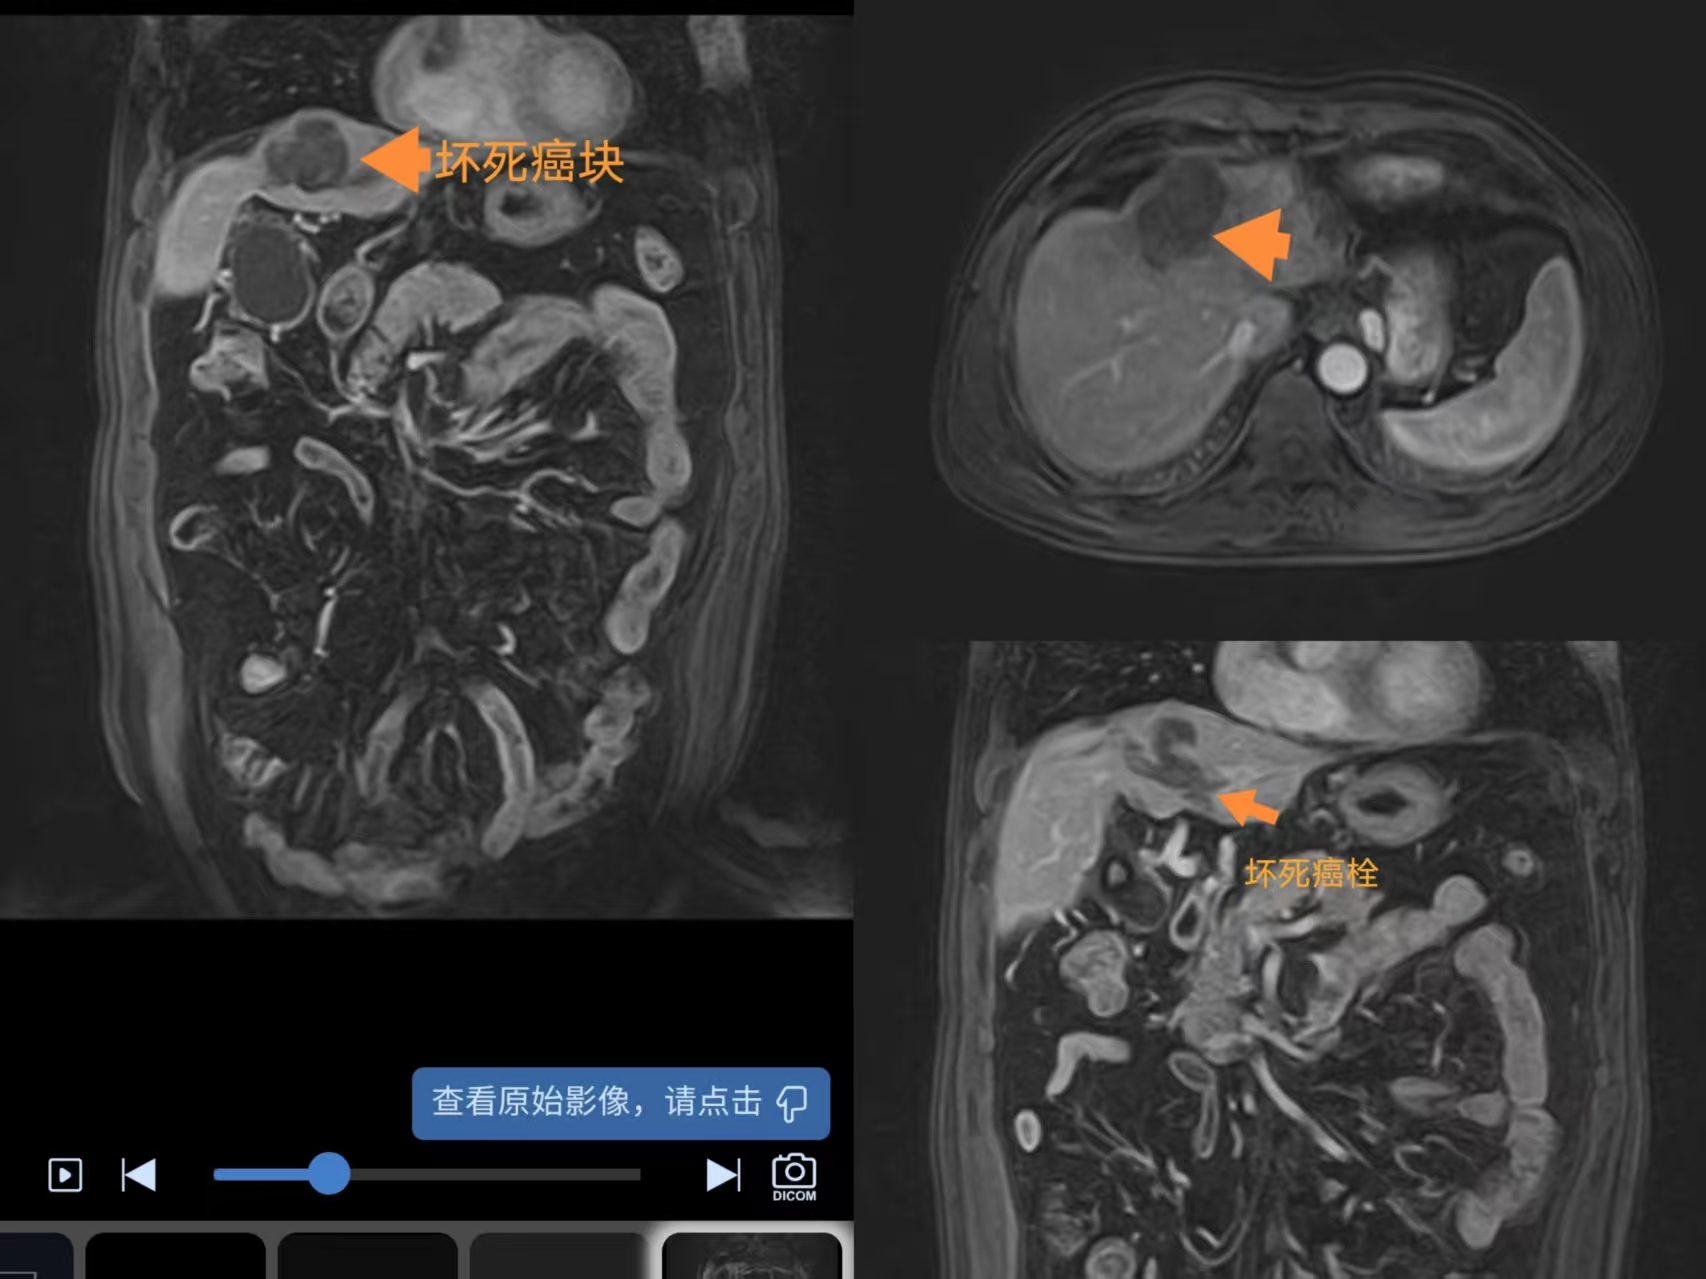

2025年2月16日杨先生如期来到成都聚焦超声医院,进行第二次疗程治疗。2025年3月21日于当地医院复查:肝肾功未见明显异常,肿瘤标志物正常范围,磁共振显示肿瘤和门脉癌栓呈消融坏死表现,但考虑到肿瘤浸润性生长,建议再次对肿瘤边缘部分行巩固消融治疗,扩大消融范围,更好的控制肿瘤,2025年4月27日再次来院进行聚焦超声消融治疗。(下图为2025年3月21日复查磁共振)

2025年8月5日再次传来复查消息;从确诊至今,都只结合乙肝抗病毒药物、保肝药物、靶向药物综合治疗,从未行化疗治疗。肝肾功未见明显异常,肿瘤标志物正常。(如下图)

2025年12月3日,在当地医院复查血和磁共振评估:肝肾功能、肿标未见明显异常,磁共振显示肝脏癌块和门脉癌栓呈消融坏死表现。目前身体综合情况佳,日常生活状态如正常人,也无不适症状,持续随访观察。